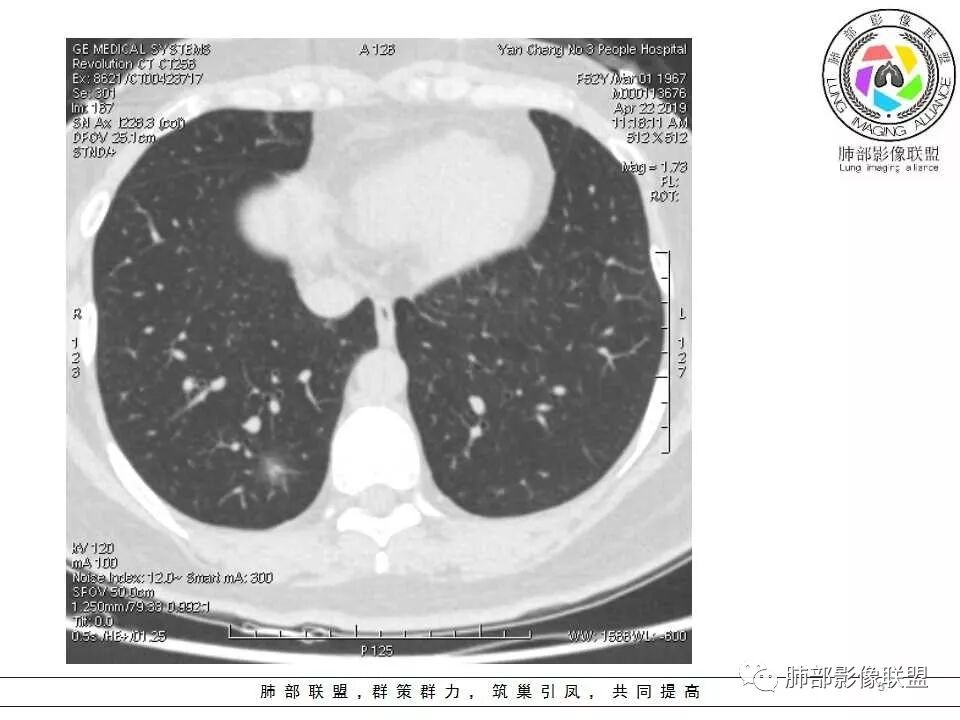

晨读:52f,体检发现右下肺结节,空洞、周围晕征(磨玻璃),局部血管影增粗,考虑1.真菌感染;2.GPA或不典型单发转移待排。

晨读:体检发现肺部结节,胸部CT:右下肺混合密度结节,结节中心空泡,壁光滑,结节边缘模糊,软毛刺,结节血管相对清楚,考虑良性结节可能,抗炎后复查。

右下肺混合磨玻璃结节,其内见空洞,空洞壁光滑,结节周围可见晕征,可见增粗血管,首次体检发现患者无症状,还是建议抗炎2周,1个月后复查,鉴别腺癌。

右肺下叶混合磨玻璃结节,边缘清晰,有分叶,毛刺,内见空泡。考虑腺癌。常规可以抗炎后复查。

横断位看上去晕很模糊,冠矢状位重建后却比较清晰,所以单次CT检查蛮难定的,中心透亮区一定是空洞吗?我怎么觉得是一支气管壁有增厚,管腔有轻度扩张的支气管,第一感觉还是炎性结节吧,PC可能大,一定要否定腺癌也不敢,一个月左右复查。

体检发现肺部结节,右下肺混合密度结节,结节中心空泡,壁光滑,结节边缘模糊,血管在结节内增粗,矢状位前基底段还有一片磨玻璃影,所以考虑良性结节可能,炎性肉芽肿?抗炎后复查。腺癌合并炎性改变待排。

晨读病例,右肺下叶小结节病灶,内可见光滑空洞,周围可见边缘模糊磨玻璃影,首先考虑感染性病变,真菌或结核可能,鉴别腺癌,后者小病灶空洞少见,周围磨玻璃影清晰,胸膜凹陷征。

病灶大部分磨玻璃边界是模糊的,但有些地方还是比较清楚,腺癌是不能完全排除的,建议1个月后复查。

mGGO,周围有晕,边界不清,空洞,收缩力不强,血管通过走形正常,首先考虑炎性结节,抗炎和复查。筛查真菌。

内部低密度是空洞还是扩张的细支气管有疑问,边缘有的层面清楚有的层面模糊,恶性待排吧。

右肺下叶混合磨玻璃结节,边缘清晰,有分叶,毛刺,内见空泡。考虑腺癌。

我未见过的类型,CT征像良恶参半。女性,52岁,腺癌的好发人群。良性征像外周纯磨玻璃影很大,而且境界欠清晰。恶性征像,中央薄壁气囊边缘实性增厚,而而且厚薄不均匀。结合性别年龄,腺癌首先考虑,处理:随访3-6月,看看实性部分有无增多,应该不影响生存率。

磨玻璃结节,中央有空洞,周围晕征,磨玻璃血运明显,考虑腺癌,鉴别隐球菌。

晨读:结节伴晕,晕模糊,内有小空洞,周边还有片状模糊影,支持首先考虑炎性,临床会先抗感染治疗后复查。

晨读:右下肺结节,结节中心小空洞,壁光滑,结节周围有晕,边缘模糊,其他基底段亦可见斑片磨玻璃影,考虑炎性肉芽肿。隐球?寄生虫?

晨读:中老年女性,体检来诊。右肺下叶后基底段近胸膜下mGGN,其内实性成分似见毛刺及分叶,并见空泡征,周围GGO边界清楚,近肺门端见血管影伸入病灶并略显扩张,病变与支气管关系观察欠佳。多考虑恶性,腺癌可能性大。鉴于首次检查,常规建议抗炎治疗后复查,观察病灶变化情况,再决定下一步诊疗方向。

晨读,中老年女性,右下肺混合磨玻璃结节,边界模糊,内有空泡,张力高,考虑支气管扩张,周围血管相连,稍有增粗,考虑良性病变,细支气管扩张畸形并周围炎。腺癌待排。

晨读,女,52岁体检发现结节,右肺下叶见磨玻璃样结节影,边缘见毛刺,病灶内可见小空泡影,考虑腺癌可能,待除外炎性病变。

病灶内低密度像扩张的支气管,整体被病灶包围,可以定为空泡,PC没有这么大的牵拉,曲霉的话病变范围太小,而且是体检发现。病灶周围磨玻璃似清非清,病灶下缘磨玻璃是明确清晰的,因此诊断倾向于粘液腺癌,比较心虚的地方是没有抗炎复查。

右肺下叶后基底段混合型磨玻璃结节,边缘见晕征,内见小空泡/空洞,其内壁光整,与支气管关系不密切,常规考虑炎性肉芽肿病变,结核/隐球菌可能,腺癌待排,建议抗炎1月后复查。

右下叶后基底段混合密度结节,边缘磨玻璃模糊,晕征,中心实性成分似有多个小结节融合,收缩力不明显,中心空泡样改变内缘光滑,考虑小空洞,综合考虑良性炎性结节,隐球可能,结核与曲霉待鉴别。抗炎后复查或穿刺活检。

右肺下叶混合磨玻璃结节,中心有小透光区,壁光整,磨玻璃边缘模糊,收缩力不明显,考虑炎性结节,抗炎治疗后复查,代排隐球菌。

右肺下叶基底段胸膜下小结节,周围模糊晕征,其内光滑囊腔影,考虑小空洞,其内血管走形自然,周围软毛刺,常规考虑炎性结节,隐球可能性大,建议抗感染后复查,鉴别粘液腺癌。

从那么多天以来的读片结果看,不要走寻常路,各位老师考虑炎性的多,小隐球结节还是实性的多(见得少不知道对不对),空洞张力较高,那我考虑腺癌。